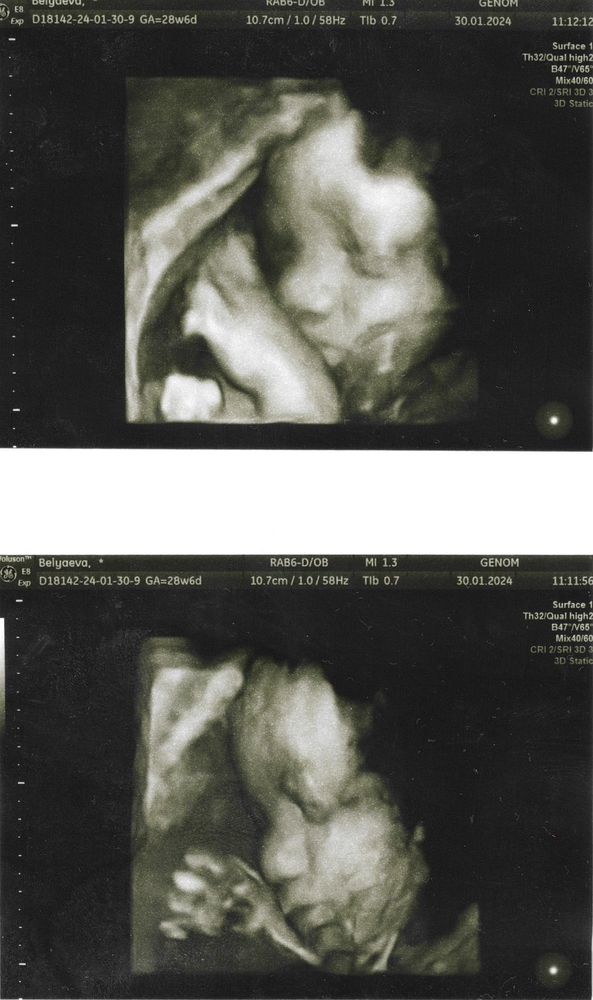

Что произошло за время, пока в дневник не писала?

Встретила 30 недель, вышла в декретный отпуск. Тогда же сделали первый КТГ - плохой (монотонный). А на следующий день второй КТГ - хороший (распихала ребёнка тычками вбок и белевской пастилой)😂